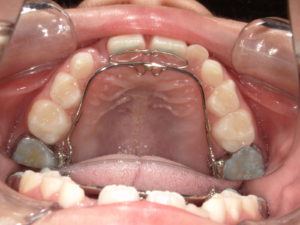

| 治療方法 | リンガルアーチによる前歯の被害改善。 |

リンガルアーチで1カ月半で動きました。